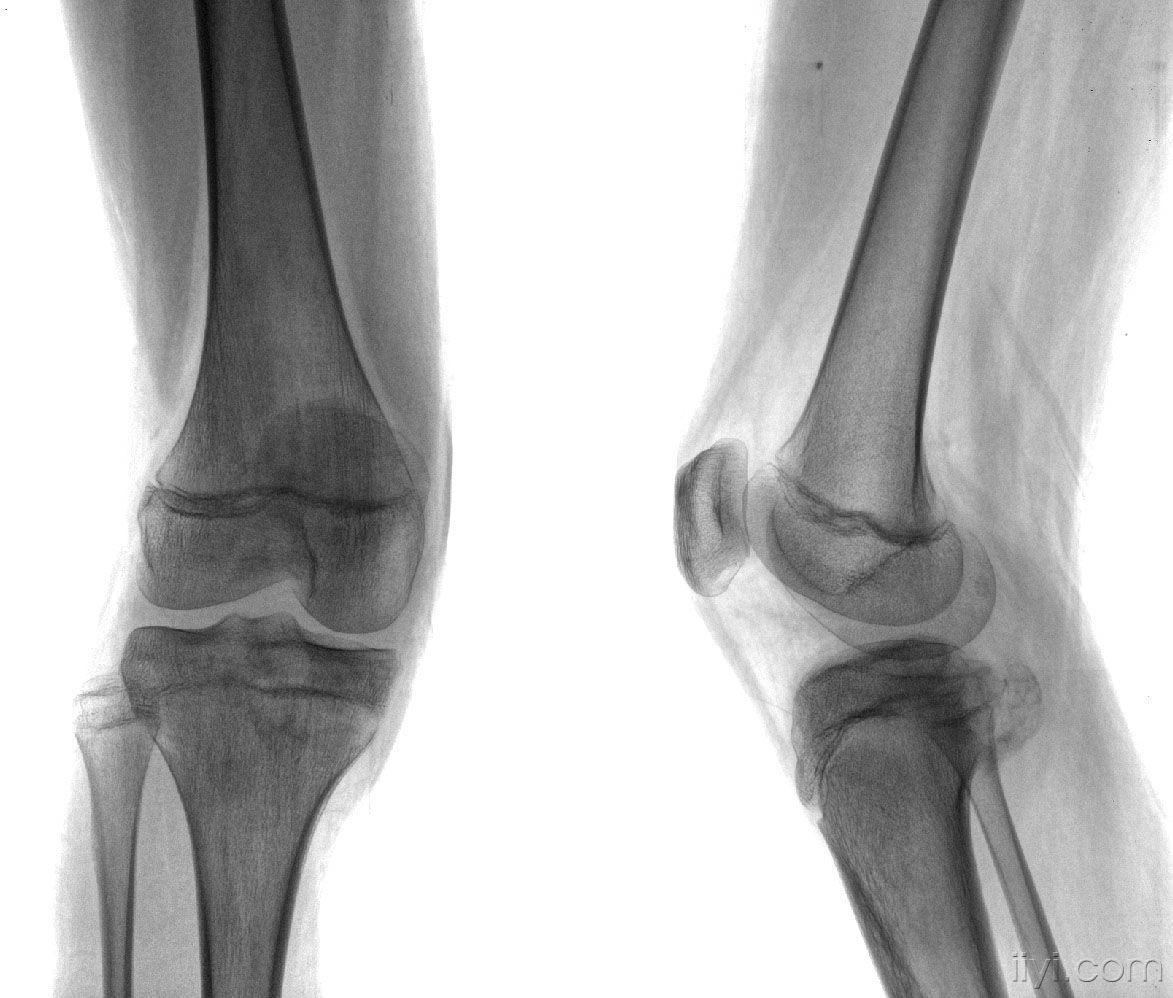

女,14岁,膝关节外伤后疼痛4月余。